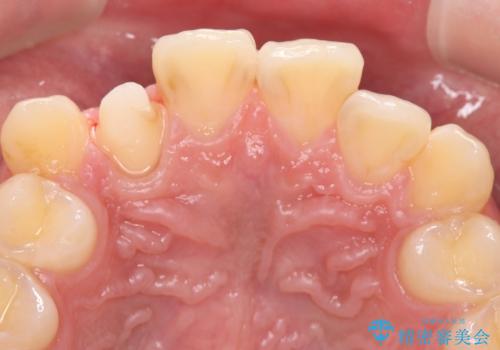

- 主訴:右上の前歯が何しなくても痛い

右上2番の歯に自発痛を認め、症状や歯髄診・レントゲン像から不可逆性歯髄炎と診断し、精密根管治療から歯冠補綴まで行うこととなりました。

初診時に歯髄診断を行い、不可逆性歯髄炎と診断し抜髄から補綴修復までの流れを説明し、精密根管治療、ファイバ-コア築造、オールセラミッククラウン(St)修復を行うこととしました。